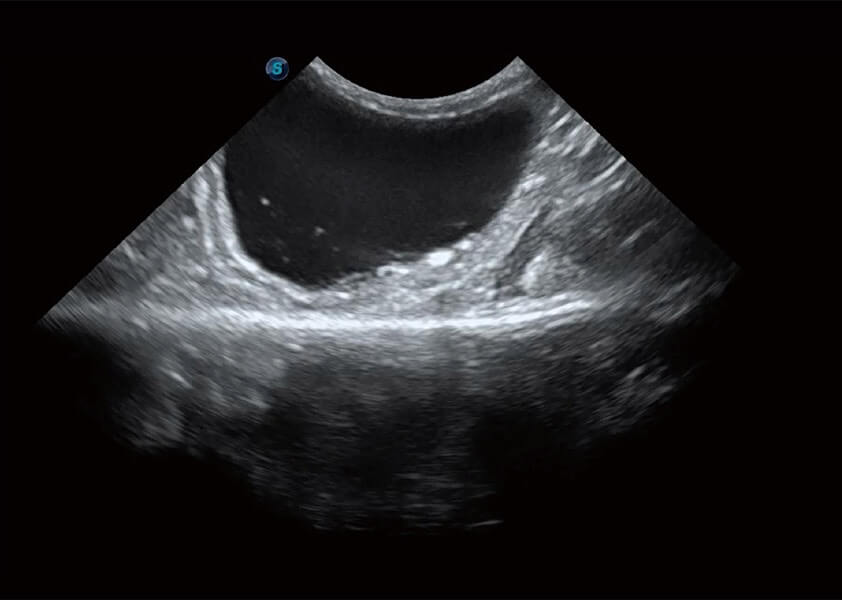

ProPet 60 作為一款高端臺(tái)式動(dòng)物超聲設(shè)備,為動(dòng)物醫(yī)生的日常診斷提供了一系列貼合動(dòng)物臨床需求、解決臨床實(shí)際問(wèn)題的高級(jí)成像功能。憑借全系列高清探頭,滿足醫(yī)生對(duì)腹部、心臟、生殖、淺表、肌骨等成像的所有需求,切實(shí)幫助您提升檢查效率,提高診斷信心。